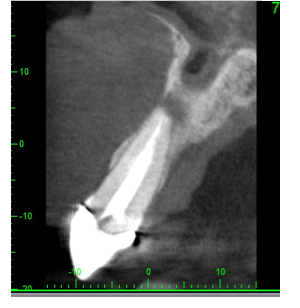

• Peri-apical lesion UR1 seen on radiograph

• RCT carried out 10 years ago

• Asymptomatic

• No clinical signs

CBCT scan OF UR1 Site, peri-apical cyst?

• Strict criteria is no periapical area present after rct. The meta-analyses had indicated that using strict criteria for judging treatment success, a minimum follow-up period of 3 years (Ng et al., 2007)